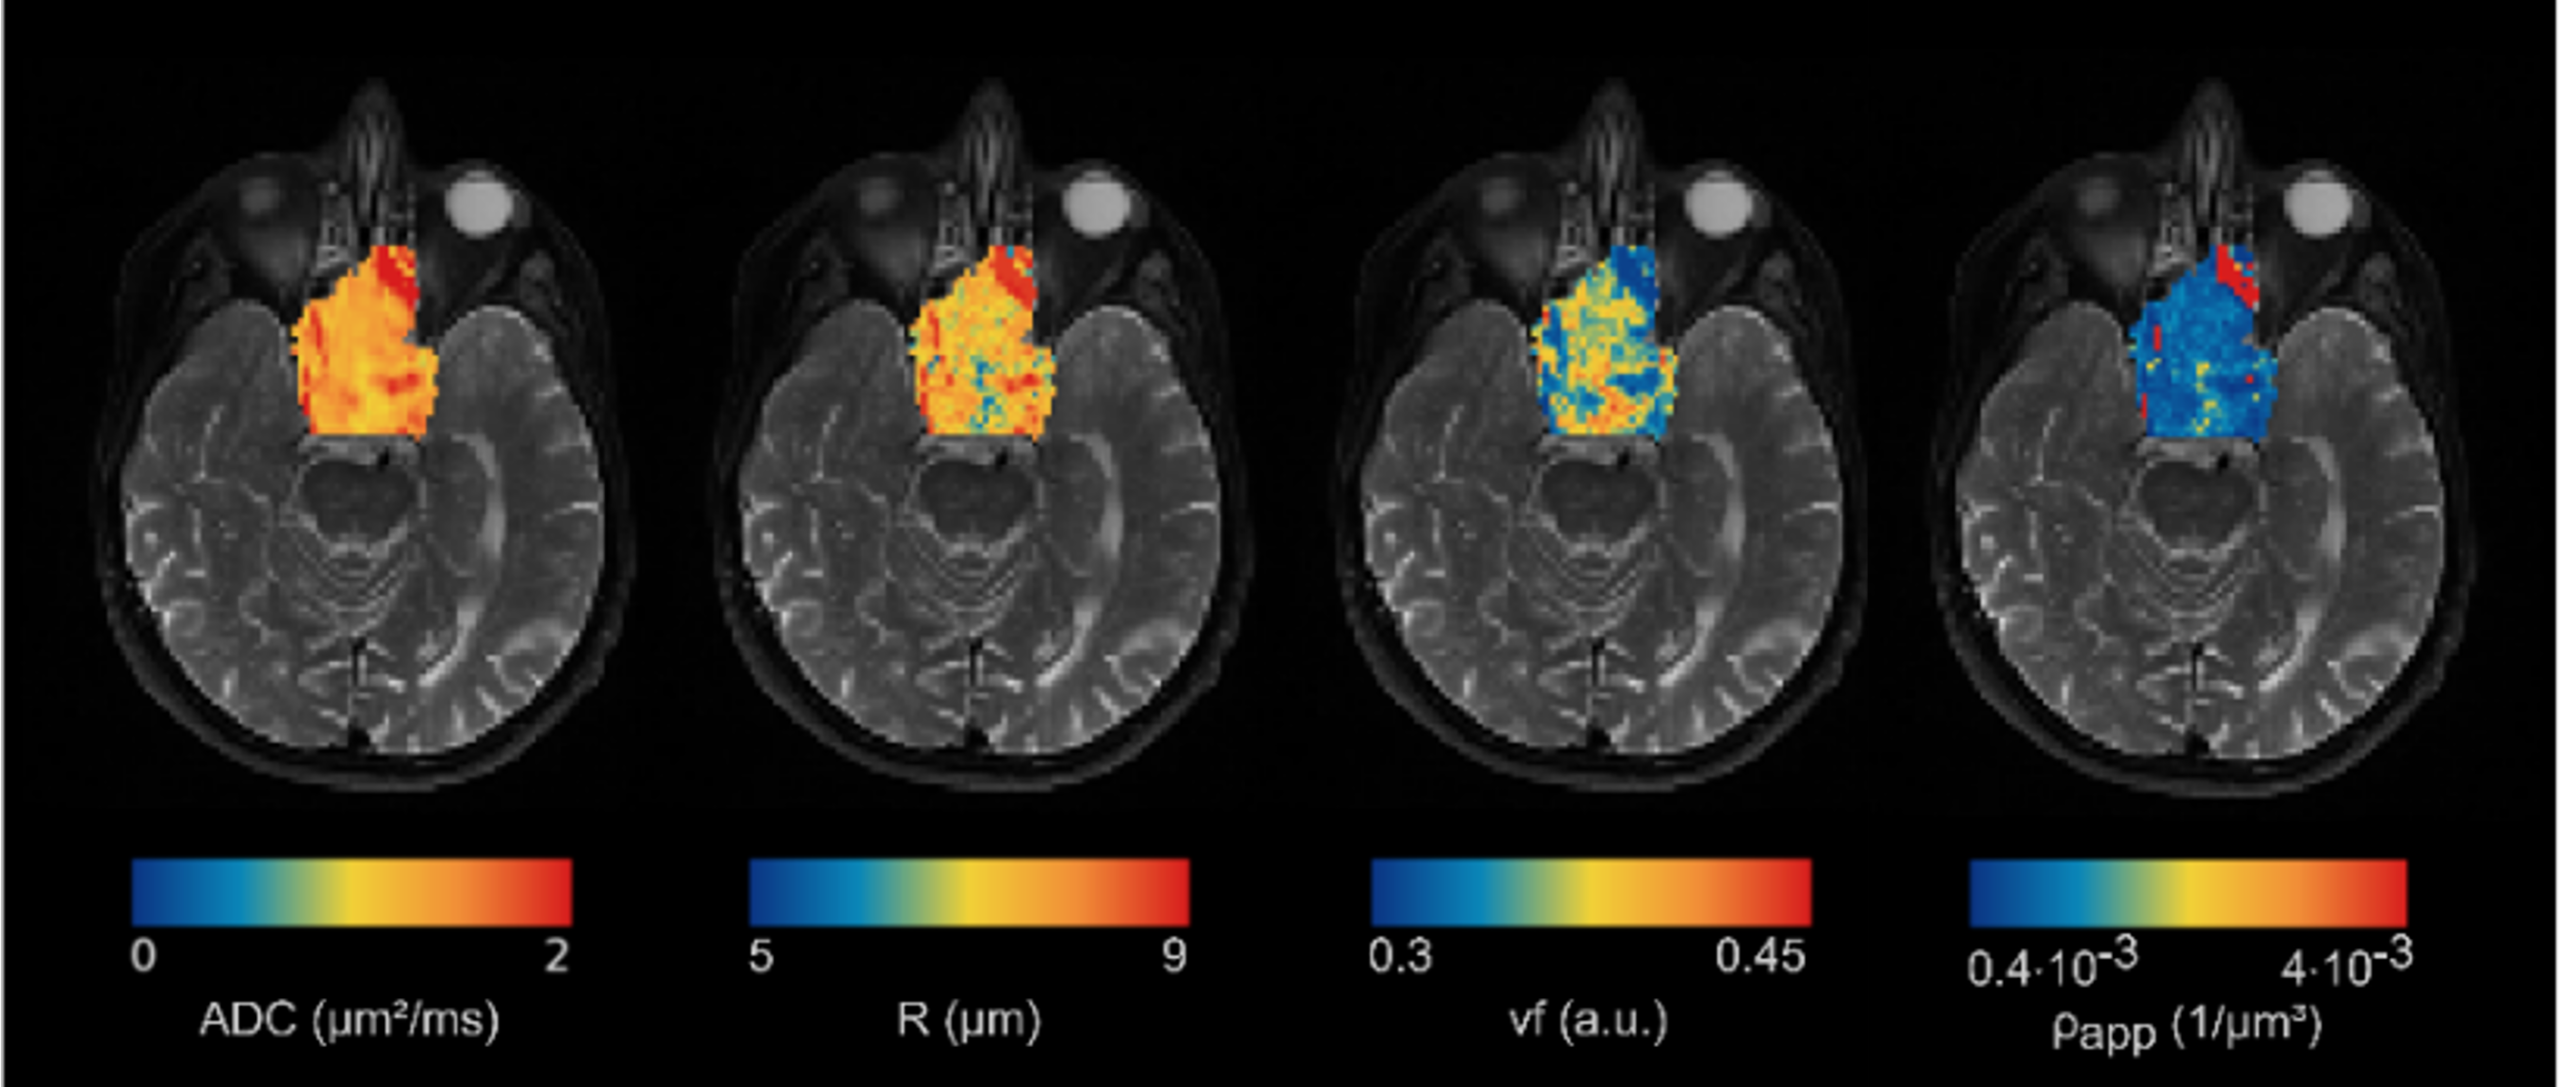

This project aims to advance PT treatments by integrating imaging biomarkers derived from quantitative Magnetic Resonance Imaging (MRI) into personalized PT, by implementing multi-scale models able to characterize tumour microstructure and its interactions with the radiation beam.

First, advanced computational models will be developed to extract macro- and micro-scale imaging biomarkers from quantitative MRI data, capturing tissue characteristics both at the voxel level and at sub-voxel resolution. These biomarkers will then be integrated into multi-scale modelling frameworks, including statistical methods, machine learning approaches, and Monte Carlo simulations. The capability of these models to characterize tumours and predict treatment outcomes in PT will be assessed using clinical parameters and biological analyses. Finally, the project will translate these findings into personalized treatment plans tailored to the biological profile of each individual tumour.